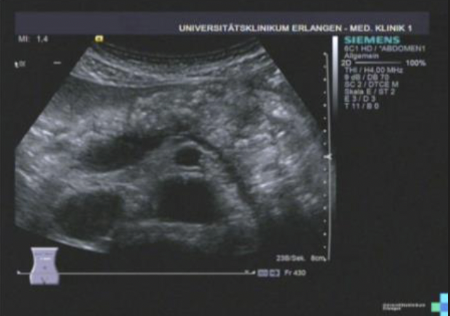

Path?

Chronic Pancreatitis (Scarring on body)